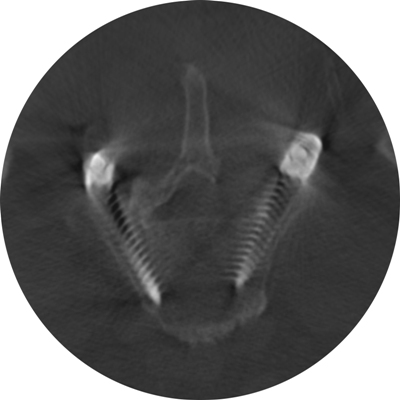

Astfel, în urma unui număr mare de investigaţii suplimentare, a fost luată decizia de a folosi un abord chirurgical numit ”fuziune intervertebrală transforaminală”. Tehnica dată este mai complicată şi mai solicitantă faţă de dotarea tehnică a blocului de operaţii şi a abilităţilor echipei chirurgicale, însă oferă un şir de avantaje pentru pacient.

Deoarece pacientul a fost operat anterior de 2 ori, utilizarea aceluiaşi coridor chirurgical tradiţional putea fi însoţită de un risc mare de leziuni a nervilor şi vaselor în canalul spinal. De aceea, a fost aleasă o cale mai puţin utilizată în practica cotidiană, dar care a fost cea mai raţională pentru pacientul dat, aşa-numitul abord paramedian transmuscular sau abordul prin spaţiul Wiltse.

Este un caz fericit pentru pacientul din Italia şi de succes pentru secţia Neurochirurgie, dar şi pentru întreaga instituţie medicală, or, astfel de intervenţii complicate au devenit posibile în Republica Moldova în urma deschiderii noului Bloc chirurgical în luna mai curent, prin intermediul căruia ţara noastră a obţinut facilităţi şi posibilităţi care au existat pînă nu demult doar în centrele medicale contemporane performante din lume. Astfel, sala de operaţii Hybrid a blocului dispune de metode de neuroimagistică intraoperatorie şi sisteme de monitoring şi neuronavigaţie, sisteme specializate de implanturi din titan şi instrumente chirurgicale, echipamente pentru disecţie osoasă. Acest complex chirurgical este completat de un departament ultradotat de anestezie şi neuroreanimare, care asigură o parcurgere perioperatorie fără complicaţii.